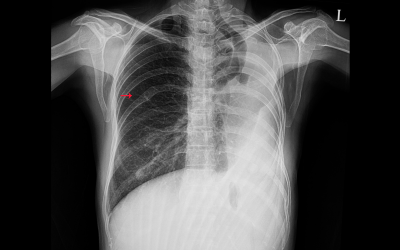

Pleural Effusion

Latest Diagnostics

Including digital imaging (CT, MRI), cancer tumor markers, and endoscopy to ensure precision of diagnosis to the last detail.

In-House Pathology and Histopathology

Quick biopsy reports and cell analysis enable quick decision-making, especially for cancer care.